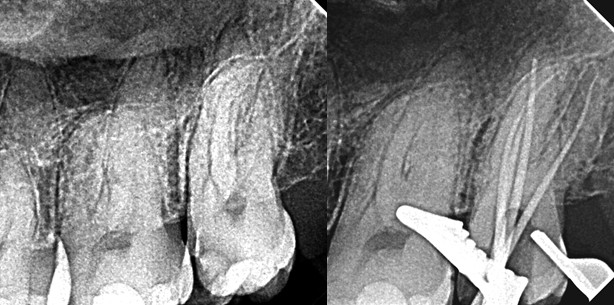

Die präoperativen Röntgenaufnahmen zeigten eine tiefe kariöse Läsion auf der mesialen Seite des Zahns. Außerdem war zu sehen, dass der Zahn drei Wurzeln hatte, und zwar eine mesiale und eine distale Wurzel mit jeweils mäßiger Krümmung im apikalen Drittel sowie eine gerade palatinale Wurzel. Mein Behandlungsplan war eine Wurzelkanaltherapie in einer Sitzung. Nach der Lokalanästhesie und dem Anlegen des Kofferdams wurde unter einem zahnärztlichen Operationsmikroskop die Zugangskavität präpariert. Dabei stellte sich heraus, dass es vier Kanäle gab, was im Mittelmeerraum beim zweiten oberen Molaren häufig der Fall ist. Hier wurden zwei Kanäle in der mesialen Wurzel und je einer in der palatinalen und der distalen lokalisiert. Die MicroOpener Feile 0,10 mm/.06 (DENTSPLY Maillefer, Ballaigues/Schweiz) erleichterte die Lokalisierung.

Abb. 3: Postoperative Röntgenaufnahme; alle Kanäle sind konisch ausgeformt; im apikalen Drittel des palatinalen Kanals sind mehrere dicht gefüllte Ausgänge erkennbar.

Abb. 4: Ein weiteres postoperatives Röntgenbild bestätigt die Resultate in den vier Hauptkanälen und den Seitenkanälen des palatinalen Kanals.

Füllung des Wurzelkanalsystems

Der erste Schritt der Wurzelkanalfüllung ist die Einpassung feiner Guttaperchastifte in die mesialen und distalen Kanäle und eines mittleren in den palatinalen Kanal. Daraufhin wurden der gelbe Plugger des Calamus-Systems (DENTSPLY Maillefer) an die mesialen und distalen Kanäle und der blaue Plugger an den palatinalen Kanal schrittweise so angepasst, dass sie sich bis 5 mm vor der Arbeitslänge einführen ließen. Nach dem Trocknen der Kanäle und der Applikation des Sealers erfolgte eine vertikale Kondensation. Die postoperativen Röntgenbilder zeigten, dass der ursprüngliche Kanalverlauf vor allem im apikalen Drittel der mesialen und distalen Kanäle genau beibehalten wurde und die Kanäle gut zentriert und optimal gefüllt waren. Im apikalen Drittel des palatinalen Kanals war eine 3-D-Füllung des Kanalsystems sichtbar, mit mehreren dicht gefüllten Foramina, was ein Beleg dafür ist, wie wirkungsvoll die Reinigung sein kann, wenn mehr Zeit auf das Spülen verwendet wird und die Spülflüssigkeiten aktiviert werden.